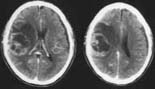

‚U‚O‘ã‚Ì’j«‚Ì_ŒoäPŽî‚Å‚·B

”]‚̉^“®‚ðŽi‚é•”ˆÊi‰^“®—Ìj‚ÉÚ‚µ‚ÄŽîᇂª

‚Å‚«‚Ä‚¢‚½‚½‚ß‹­‚¢•Жƒáƒ‚ƈӎ¯áŠQ‚Å”­Ç‚µ

‚Ü‚µ‚½B